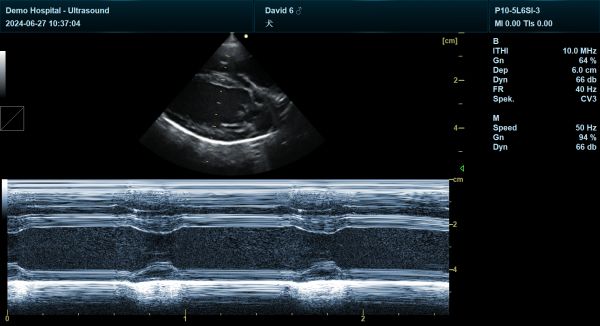

YHK-C90可以用于动物腹部、心脏、产科、小器官、血管、肌腱等方面的检查。支持的动物类型有猫、狗、牛、马、羊...